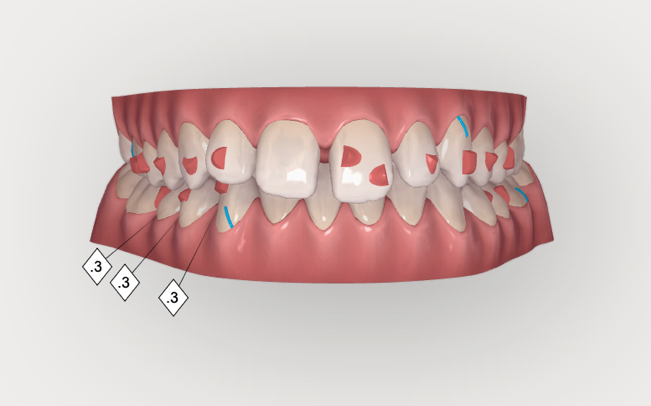

Impronta e scanner tridimensionale

Le immagini tridimensionali delle arcate dentarie vengono elaborate con un software estremamente evoluto che ci permette di pianificare il piano di trattamento ideale e di visualizzarne le fasi.